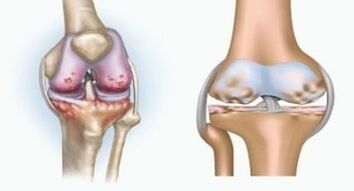

Both pathologies affect the joints, but differ in the nature of the changes.

Arthritis is an inflammation of the connective tissue - a synovial membrane that contains many vessels and provides lymph flow.The inflammatory process leads to a violation of the nutrition of articular tissues, as a result of which the production of articular lubrication - synovial fluid is limited.

Arthrosis is a degenerative-dystrophic process associated with the destruction of the cartilage tissue of the joint.The cartilage is gradually destroyed, dry, the distance between the bones of the joint decreases, which is the cause of pain.In severe forms, destruction affects bones.They become more porous, lose their density, become fragile.